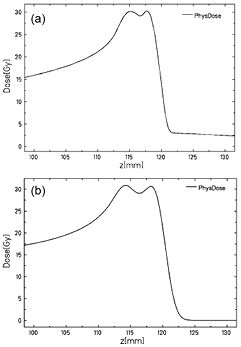

Standard image High-resolution imageThe beams were generated using the linac-synchrotron combination at the HIT facility. Comparable treatment plans were designed with protons and 12C-ion beams, in order to irradiate the brain with a homogeneous dose distribution from a spread-out Bragg peak (SOBP) target volume of 10 mm lateral and 5 mm longitudinal extension in water, delivering 30 Gy physical dose (figure 2). Using the active raster scan system, the two SOBPs were delivered at once to each mice pair, immobilized in a custom-designed plexiglas holder, with special care to adjust the lateral position of the treatment field to the middle of the mice skull and the beginning of the SOBP at the mice entrance skin surface using a 10 cm thick plexiglas degrader along the horizontal beam direction. Due to the synchrotron-based beam delivery, the irradiation consisted of a few particle spills of different energy. Specifically, four iso-energy slices (E = 241.8 − 246.6 MeV u−1) with an average lateral beam size of 4.4 mm (FWHM) were delivered with carbon ions for each SOBP, whereas six energy slices (E = 125.7 − 128.7 MeV u−1) with an average spot size of 12.8 mm (FWHM) were used for protons. Reproducibility of the lateral position of the irradiation field was in the order of ± 1 mm, which is somewhat worse than the achievable accuracy of ± 0.5 mm in the positioning of individual mice with the help of a holder and room laser. Relevant parameters for evaluation are total irradiation time (Tirr), elapsed time between the end of irradiation and beginning of PET-measurement (Toff) and the length of PET-measurement (TPET) (table 1). The times between the end of irradiation and the beginning of PET-measurement were recorded using a stop watch and duration of PET-measurement was defined beforehand in the examination protocol, where intervals of 30 min were typically chosen, with 60 min and 90 min for some mice to test the influence of a longer reconstruction time.

Figure 2. Planned spread-out Bragg peak (SOBP) target volume of 10 mm lateral and 5 mm longitudinal extension in water for (a) 12C and (b) proton irradiation.